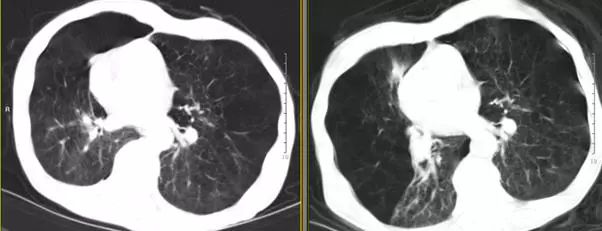

术后5天胸部CT(图7)显示右肺上叶局灶性气胸,肺大疱明显缩小,中叶未能复张,血气分析(鼻导管吸氧2L/min)提示:PH 7.425,PaO261.8 mmHg,PaCO246.8 mmHg,HCO3 -30.0 mmol/L,遂出院观察。住院期间无院内获得性肺炎、咯血、单向活瓣移位等并发症。

图7 术前2天(右)与术后5天(左)胸部CT对比